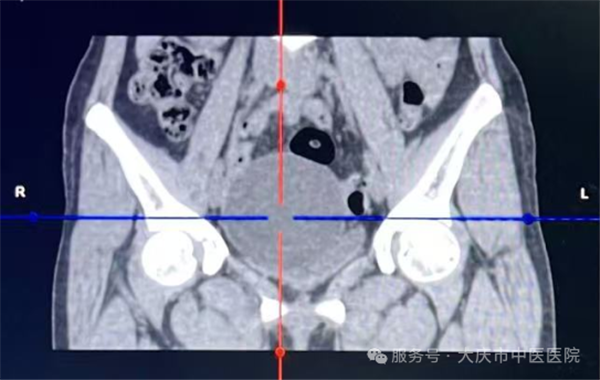

这项技术的核心优势在于“精准微创”,手术全程在超声实时监控下开展,医生通过细针经皮肤穿刺进入囊肿内部,先将囊液彻底抽出,再向囊内注入硬化剂,破坏囊肿内壁的分泌细胞,有助于降低复发风险。整个操作无需切开腹部,创伤仅为针尖大小,对周围组织影响极小。

从临床操作来看,这类手术流程规范,医护团队会严格执行无菌操作,全程监控穿刺路径与针尖位置,确保每一步操作精准可控。由于创伤极小,患者术中多无明显腹部不适感,出血量极少,整台手术耗时通常不足30分钟,能最大程度减少对正常生活工作的干扰。